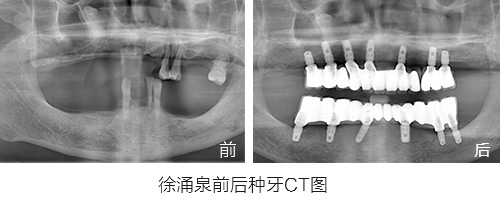

种植情况:全口种植,即拔即种,植骨

种牙时间:2015年3月(已种牙1年5个月)

种植情况:全口种植

徐先生的种牙笔记:记录一年多的种牙经历